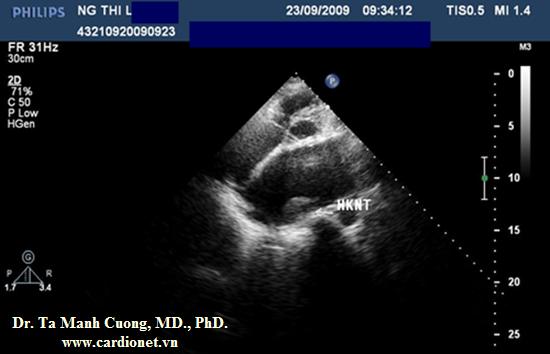

Hình ảnh khá rõ nét của huyết khối bám trần nhĩ trái, sát nơi đổ vào của tĩnh mạch phổi phải. Ở mặt cắt này ta nhìn không rõ hình ảnh van tim nhân tạo